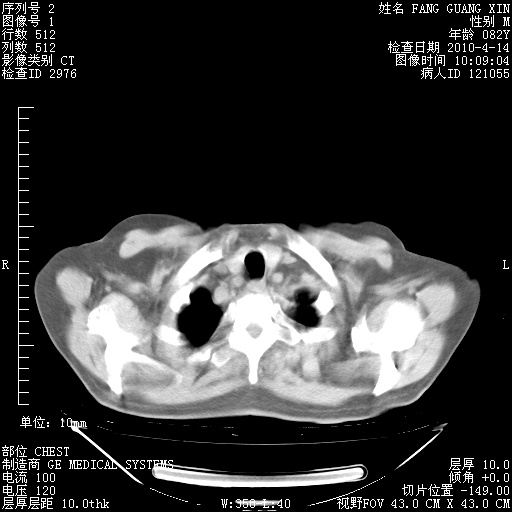

4月14日肺部CT

肺部CT平扫未见异常。